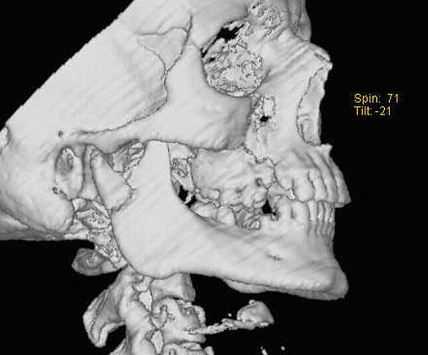

• КТ в костном окне и КЛКТ:

о Хронический вывих: атрофия суставного возвышения и уплощение суставной ямки

о КТ в костном окне и КЛКТ с трехмерной реконструкцией для оценки анатомических отношений смещенного мыщелка

(Справа) На сагиттальной КЛКТ правого и левого мыщелков у этого же пациента определяется, что мыщелки расположены спереди и сверху относительно сулавных возвышений. Обратите внимание, что мыщелки имеют нормальную форму, а кортикальная плалинка не изменена.

- Передне-медиальный вывих часто сочетается с переломом нижней челюсти

- Верхний вывих часто обусловлен травмой; мыщелок проникает в среднюю черепную ямку и может повреждать твердую мозговую оболочку

• При верхнем вывихе оцените целостность крыши суставной ямки